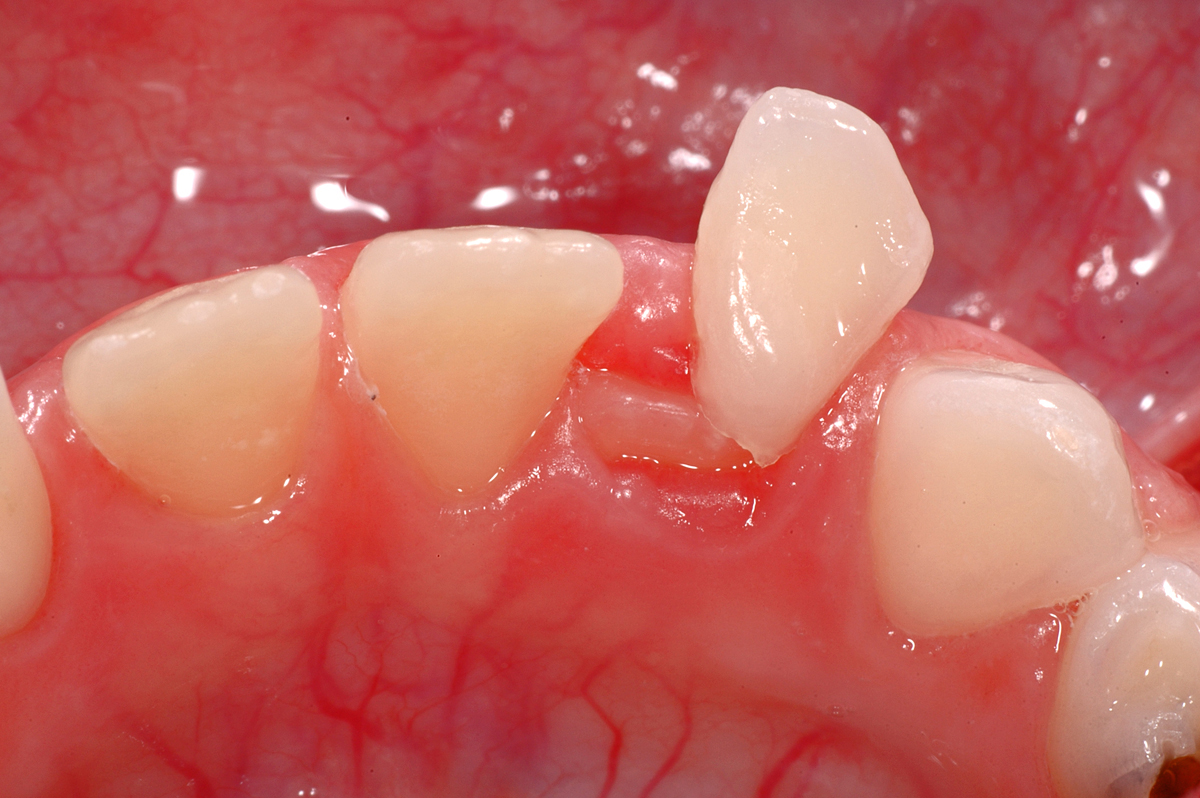

Anbei ein Fall einer knapp 6-jährigen Patientin, bei der der Zahn 42 (seitlicher Schneidezahn unten rechts) bereits durchbricht, der Milchzahn 82 aber noch vorhanden ist. Der Milchzahn ist schon sehr stark wacklig und wird demnächst aufallen. Wir nennen das «kurz vor Exfoliation».

Oft bereiten solche Situationen «Probleme», weil die scharfen Kanten, die durch das Auflösen der Zahnwurzel entstehen, bei Bewegung ins Zahnfleisch «stechen». Die scharfe Kante ist auf dem unteren Bild deutlich zu erkennen.

Diese Situation erfordert sehr selten eine zahnärztliche Intervention, hier ist eher die Zahnfee angesagt: an solchen Zähnen sollen die Patientinnen und Patienten einfach selbst ganz fest wackeln, bis die Zähne draussen sind. Damit ist dann auch das Problem der Schmerzen und des unangenehmen Gefühls behoben. Und wenn dann noch die Zahnfee was unters Kopfkissen legt, dann motiviert das vielleicht gleich für die kommenden Wackelzähne…